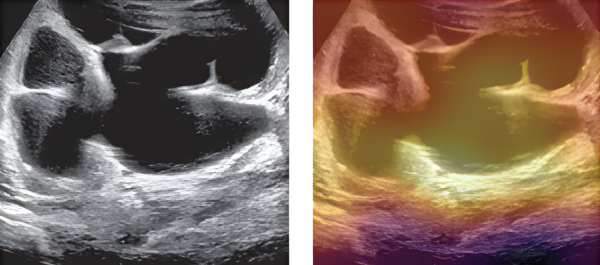

Mandy Rickard, Nurse Practitioner in the Urology Clinic at SickKids, performs and analyzes kidney ultrasounds almost daily as lead of the pre- and postnatal hydronephrosis clinic. In the clinic, she cares for up to 100 children a month with hydronephrosis, a condition caused by a urinary tract blockage that can result in kidney obstruction.

While analyzing the ultrasounds, Rickard looks at the degree of hydronephrosis and other characteristics that may suggest an obstruction that needs to be operated on. She also oversees an AI model developed to predict the severity of hydronephrosis cases and help providers identify appropriate care pathways. Over time, Rickard found that she was able to anticipate the AI model’s behaviour and intuit how it would categorize an ultrasound.

In new research published in the NEJM AI, a peer-reviewed journal from the publishers of the New England Journal of Medicine, the research team noted that Rickard's improved ability to interpret kidney ultrasounds was a direct result of her repeated exposure to the AI model. Over a three year period, Rickard reduced the number of children with hydronephrosis sent for invasive nuclear scans from 80 to 58 per cent.